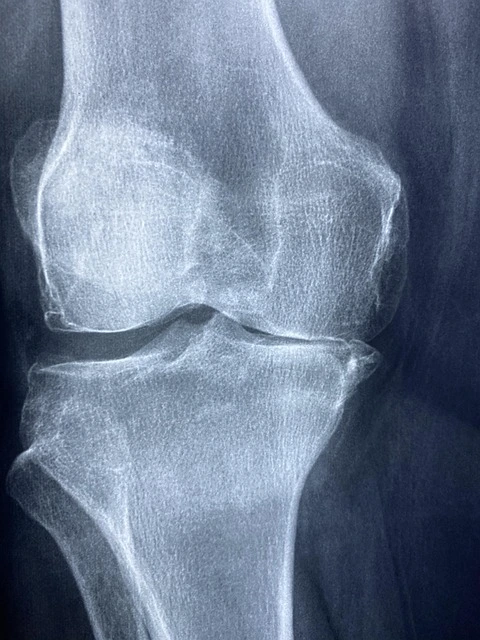

๋ฌด๋ฆ ๋ฏธ์ธ์ฒ๊ณต์ ์ด๋?

๋ฌด๋ฆ ๋ฏธ์ธ์ฒ๊ณต์ (Microfracture)์ ๋ฌด๋ฆ ๊ด์ ์ฐ๊ณจ์ด ์์๋์์ ๋, ๊ด์ ๋ด์๊ฒฝ์ ์ด์ฉํด ์์๋ ๋ถ์ ์๋ ๋ผ์ ๋ฏธ์ธํ ๊ตฌ๋ฉ์ ๋ซ๊ณ , ๊ทธ๊ณณ์์ ํ๋ฌ๋์ค๋ ๊ณจ์ ์ฑ๋ถ(์ค๊ธฐ์ธํฌ ํฌํจ)์ด ์๋ก์ด ์ฐ๊ณจ ์กฐ์ง์ ํ์ฑํ๋๋ก ์ ๋ํ๋ ์น๋ฃ๋ฒ์ ๋๋ค.

์ ํต์ ์ธ ์ฐ๊ณจ ์ด์์ ๋ณด๋ค ๊ฐํธํ๊ณ ๋น์ฉ๋ ์๋์ ์ผ๋ก ์ ๊ฒ ๋ค๊ธฐ ๋๋ฌธ์, ์ด๊ธฐ ์ฐ๊ณจ ์์์ด๋ ๊ตญ์์ ๊ฒฐ์ ํ์, ๊ณ ๋ น์ธต์๊ฒ ์ ํฉํฉ๋๋ค.